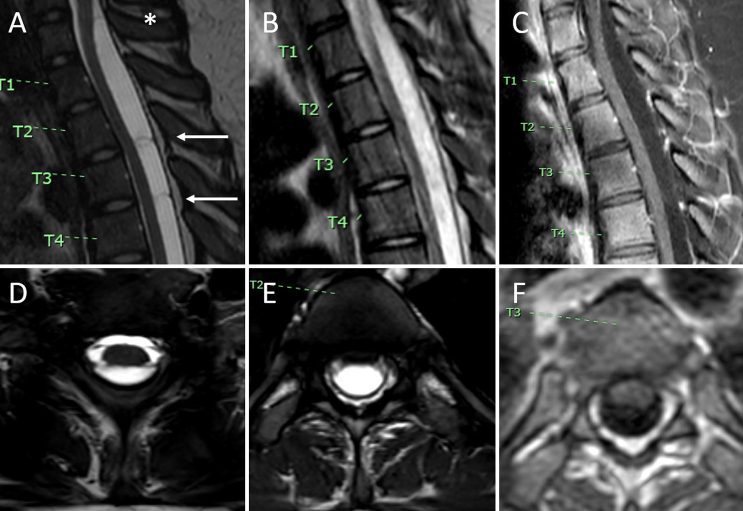

Background: Spinal arachnoid cysts can cause myelopathy through spinal cord compression. While MRI is the standard for diagnosis, traditional sequences may not clearly define cyst borders and septations, which are important for guiding surgical intervention. Balanced fast field echo (B-FFE) is an MRI sequence that highlights small arachnoid membranes within and at the borders of CSF spaces.

Observations: The authors report the case of a 13-year-old female who presented with progressive lower extremity paresthesias and weakness and urinary incontinence. MRI revealed an intradural cervicothoracic arachnoid cyst (C7-T3) dorsal to the spinal cord. B-FFE was used to identify the upper and lower borders of the intradural arachnoid cyst and its internal septations. These findings corresponded precisely with intraoperative findings and guided fenestration at the cyst's cranial, caudal, and internal septal ends. Postoperatively, the patient's symptoms resolved, and MRI confirmed the resolution of mass effect. At the 10- and 30-month follow-ups, there was no evidence of cyst recurrence clinically or radiographically.